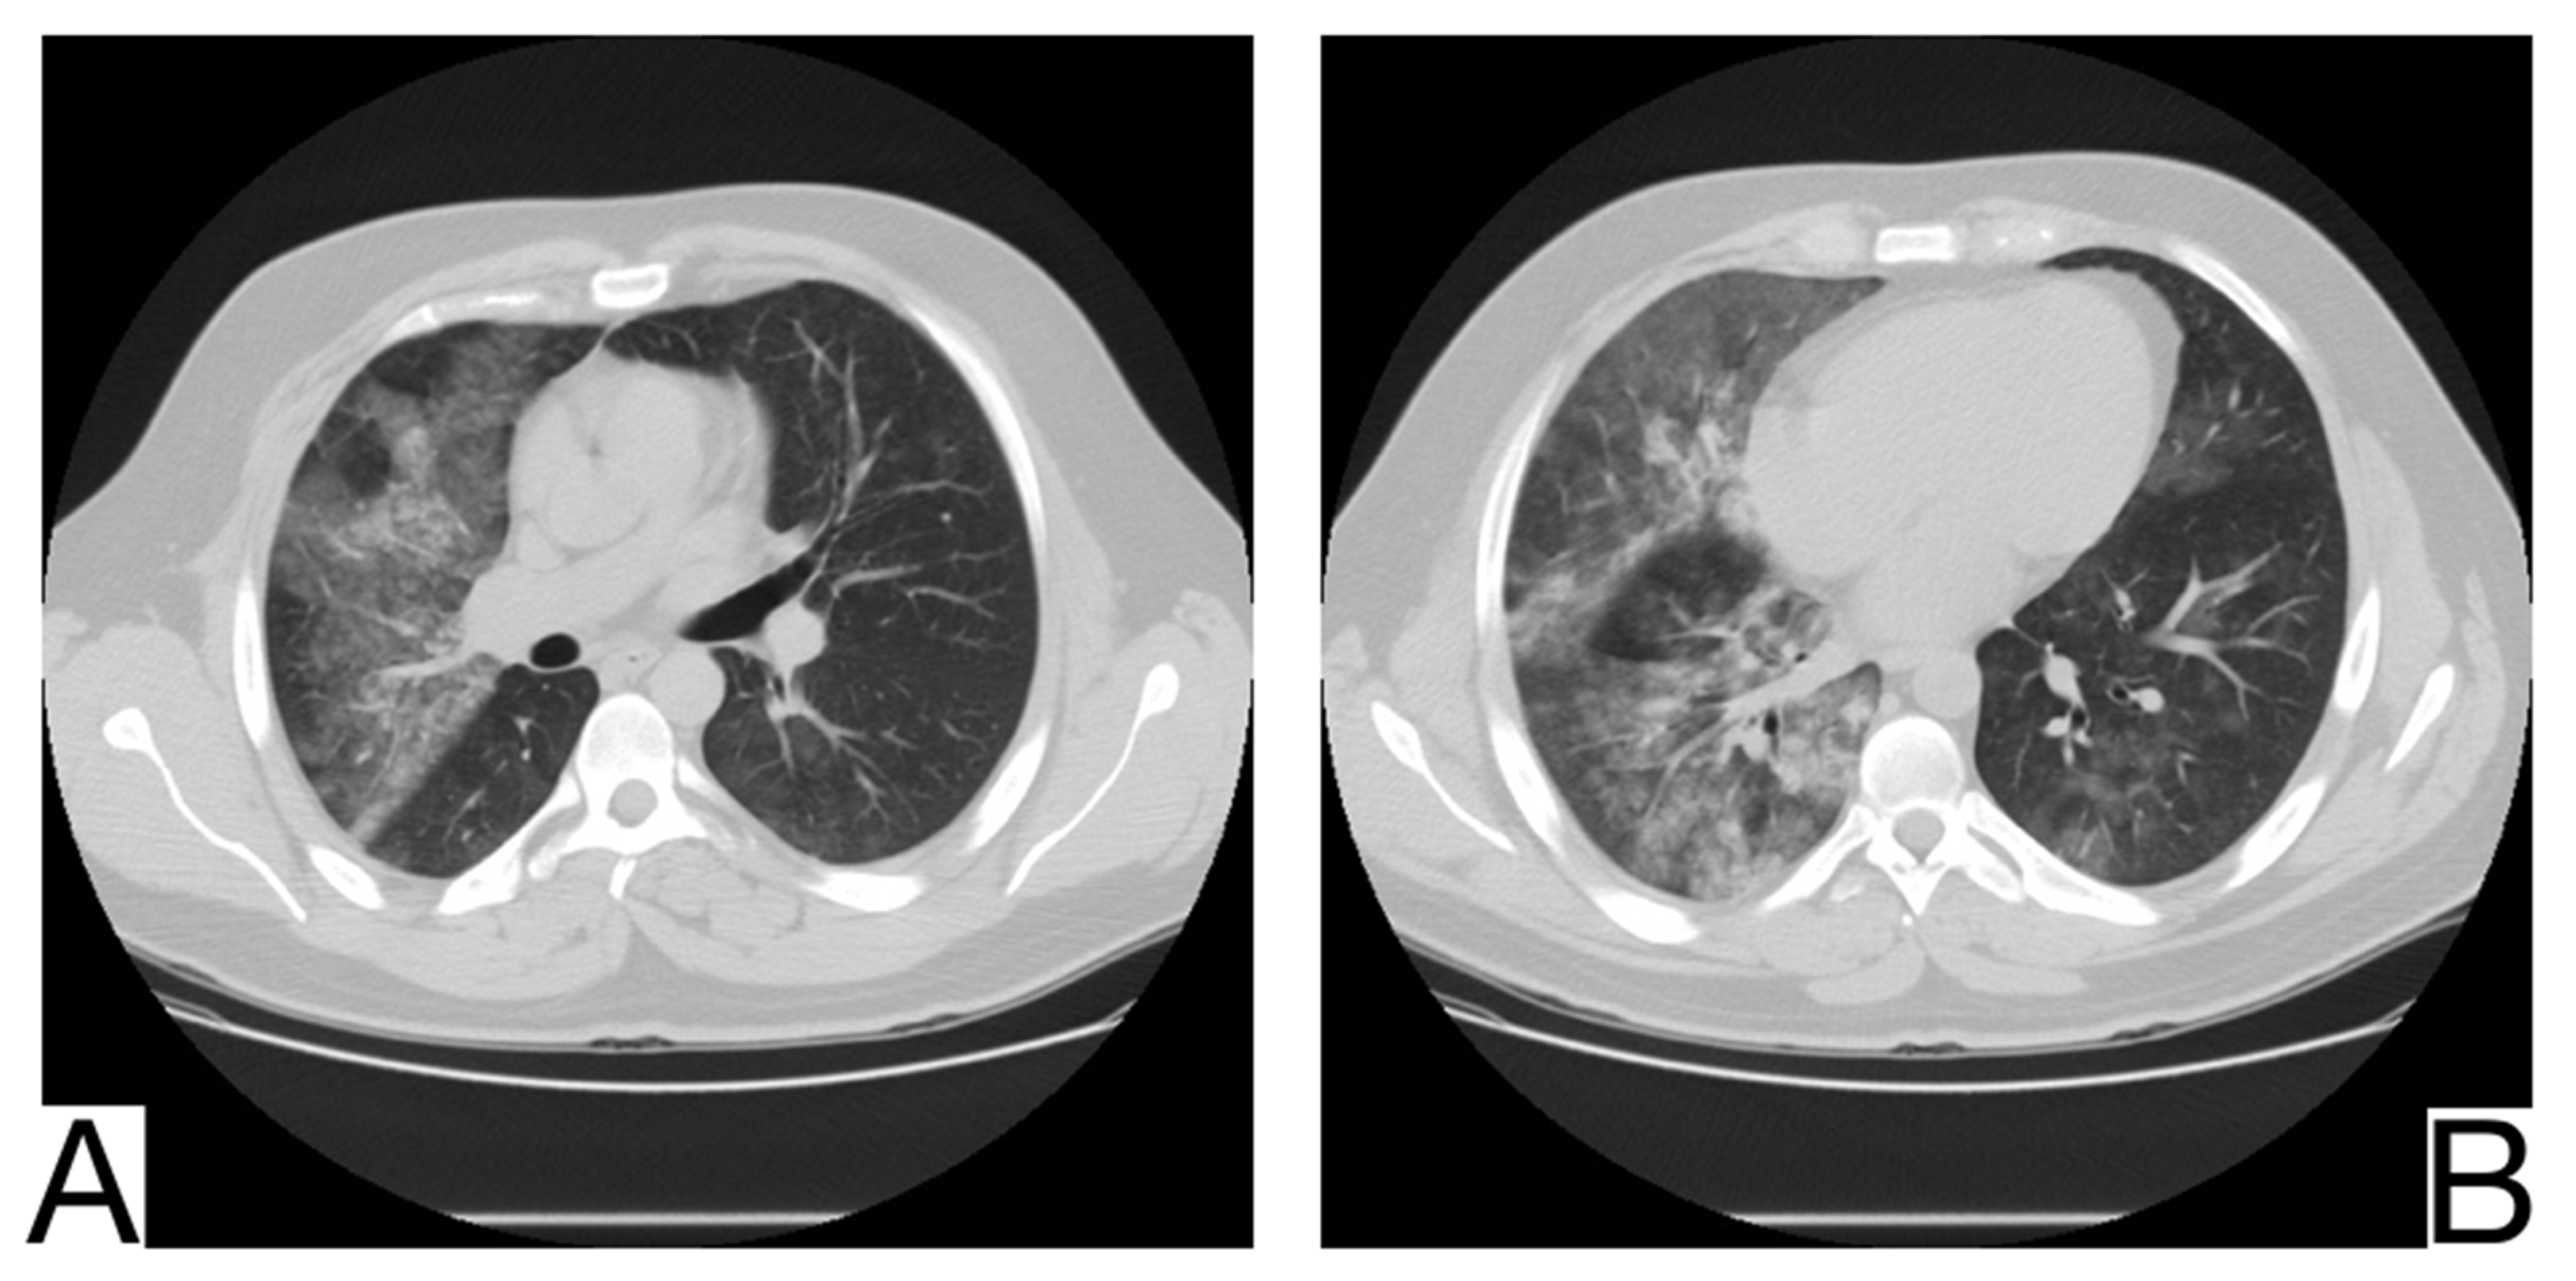

10.5.1. Acute Pulmonary Edema

There are two pathophysiological and radiological phases recognized in the development of cardiogenic pulmonary edema: interstitial and alveolar.

In addition to anamnesis, radiological features (Figure 7A,B) for differential diagnosis are the possible coexistence of ground-glass opacities, pavement, and consolidations with different times of occurrence about COVID-19 pneumonia []; the pattern of crazy pavement—diffuse, bilateral, with central disposition—and ground-glass opacities with subpleural preservation. Condensations are late and generally coexist with pleural effusions; bilateral pleural effusions, more evident in the alveolar phase of edema []; mediastinal lymphadenopathy; cardiomegaly.

Figure 7. Acute pulmonary edema (A). Ground glass opacity in mainly perihilar and dependent distribution (B). Bilateral airspace opacification in central peribronchovascular distribution and smooth interlobular septal thickening (indicating interstitial edema) and moderate bilateral pleural effusion. Note. Case courtesy of The Radswiki, Radiopaedia.org, rID: 1183 (A) and Dr. Rania Adel Anan, Radiopaedia.org, rID: 95825 (B).

Cases of acute myocarditis related to COVID-19 infection have been reported. The standard features of COVID-19 pneumonia and pulmonary edema should always raise the suspicion of myocarditis, especially in young patients.

10.5.2. Differential Diagnosis of COVID-19 Pneumonia with Acute Heart Failure

COVID-19 pneumonia usually symptoms are fever, cough, and dyspnea. Although typical imaging features for COVID-19 pneumonia are specified on chest CT (ground-glass appearance), these features can sometimes be confused with other conditions [].

One of these clinical entities is acute heart failure, characterized by fluid accumulation in the interstitial and alveolar spaces due to increased hydrostatic pressure in the pulmonary vessels. Acute pulmonary edema caused by heart failure can mimic several diseases on chest CT, leading to delays in diagnosing and treating these patients [].

Anamnesis, history of exposure to SARS-CoV-2, and symptoms such as fever, cough, and fatigue were reported in a significantly higher number of patients with COVID-19 pneumonia than in those with acute heart failure.

The distribution of lesions on chest x-ray and CT is different, with the predominance of central lesions in the AHF compared to patients diagnosed with COVID-19 pneumonia [,,].

Pleural effusion and cardiomegaly, mediastinal lymphadenopathy, septal thickening, and dilation of pulmonary veins are found in a significantly higher percentage of patients with AHF.

The distribution of lesions on chest CT, pleural effusion, and cardiomegaly can provide important information to clinicians in evaluating the differential diagnosis [,,].

Biological tests reveal it is significantly lymphopenia. In addition, patients with COVID-19 pneumonia had significantly increased levels of CRP, ferritin, LDH, and CK compared to patients with AHF, and the level of NT—proBNP is considerably higher in the group of patients with AHF. Compared to AFH, patients with COVID-19 pneumonia have higher LDH, CK, ferritin, and CRP [].